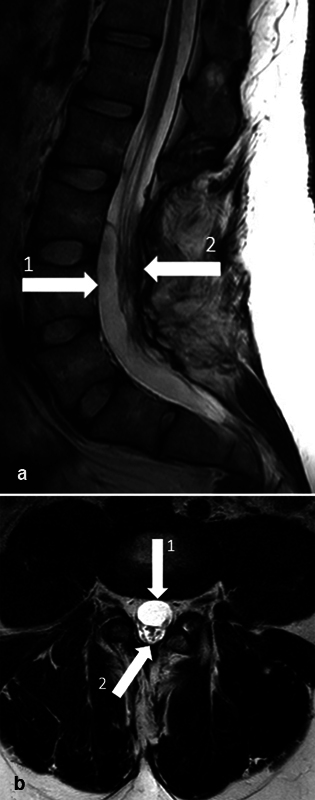

Background and importance  Selective dorsal rhizotomy (SDR) is a surgical technique to treat spasticity, mainly in children with spastic cerebral palsy (CP). In this report, a unique case of a late arachnoid cyst, causing radiating pain in the left leg, is presented. This is relevant to clinicians managing the long-term follow-up of patients who underwent selective dorsal rhizotomy (SDR). Clinical presentation  A 25-year-old male with bilateral spastic CP, who underwent SDR at the age of 7, presented with symptoms of progressive radiating pain in the left leg. Magnetic resonance imaging (MRI) revealed the presence of a large arachnoid cyst and a remarkable dorsal position of the cauda equina. After dissection of the cyst, the previously experienced radiating pain immediately subsided; however, the patient developed urinary retention and constipation. Cauda compression was ruled out by MRI. The constipation subsided quickly, and the patient performed self-catheterization until 1 month postoperatively for the urinary retention after which there were no signs of ongoing bladder dysfunction. Conclusion  Arachnoid cyst formation can be a late complication of SDR and can cause lumbosacral radicular syndrome in the late postoperative course in select cases.